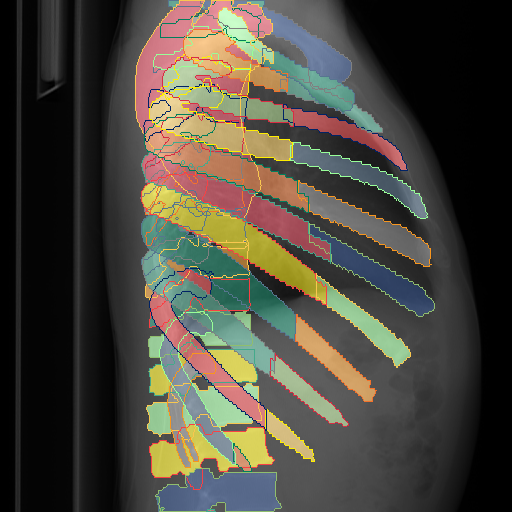

We show qualitative results for frontal projections in Fig. 2. We show a subset of classes belonging to the supercategories lungs, vascular systems, bones, and abdomen/digestive system. The predictions show minor deviations at the boundaries of the individual classes of the respiratory and vasculature system, while some inaccuracies become visible in the abdominal area. The qualitative results for the lateral projections are displayed in Fig. 2. Akin to the frontal view, the predictions show smoother borders but align with the ground truth. Apart from this, the segmentations provide matching insights on the thoracic anatomy with a slight deviation from the ground truth for both frontal and lateral views.

Fig. 2 shows quantitative segmentation results for frontal (top row) and lateral (bottom row) views. We display the class performances in the form of IoU (left), DICE (center), and Hausdorff distance (right) for each sample as a scatter plot with the mean performance for the classes shown by a line plot. Generally, we see performances for standard spinal classes, such as the thoracic vertebrae with average IoU-scores above 80%, while the average performance of rare vertebrae of the dataset belonging to the cervical and lumbar spine can drop down to 40%. In the frontal view, there exists more variance in thoracic vertebrae segmentation performance compared to the lateral view. Bone structures such as the sternum, clavicles, and scapula achieve IoUs in the mean from 85% to 95%. For ribs, we can see a noticeable performance drop for the anterior parts of the lower ribs independent of the side. The lower anterior ribs typically do not contain a large area, making them difficult to segment. This behavior is mirrored in the lateral view across the metrics. Abdominal classes can vary in segmentation quality as they occur in a nearly homogenous region. For example, while the liver or stomach are typically well-segmented, the duodenum and kidneys are more complex. Heart and Lung related classes show near-perfect segmentations with scores above 90% IoU. Breast tissue segmentation in comparison only achieves a mean of 70% mIoU. It can be noted that classes in the lateral view tend to have slightly better scores than their frontal counterparts.